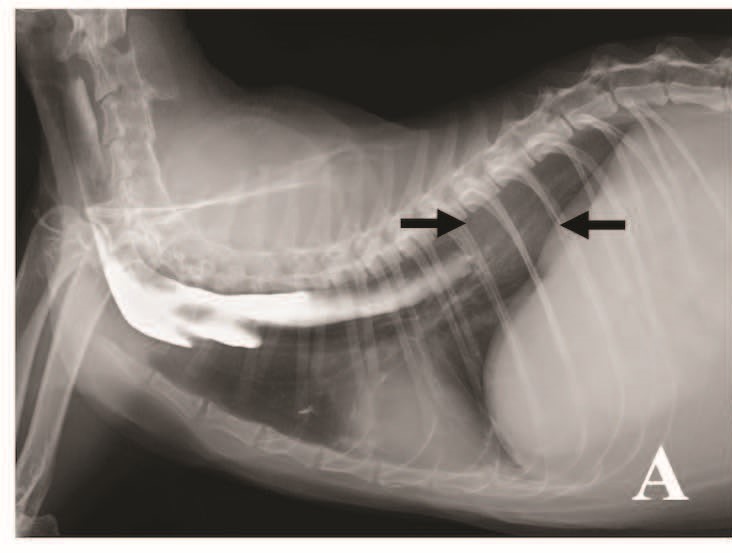

胸部X光可见食管扩张,外院造影剂残留于食管内(图1A),造影剂未进入食管远端1/3段,于膈肌上方可见约2 cm圆形肿块影。腹部X光未见异常。

图1. (A)初诊时的胸部X光片。外院食管造影使用的硫酸钡残留于食管前2/3段,造影剂未流入远端1/3,于造影中断处与膈肌之间可见圆形肿块影(箭头)。